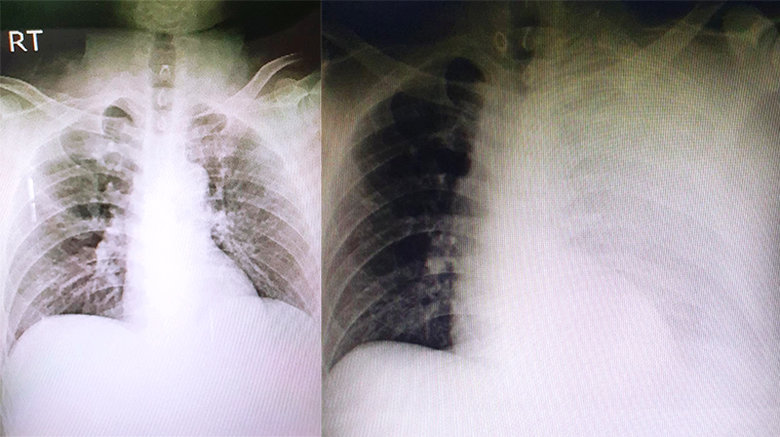

1名56歲湯姓男子近日發生車禍,被送往醫院治療,在胸部X光檢查時發現左側1根肋骨骨折,因此安排住院接受疼痛控制,2天後要準備出院時,卻還是覺得不太舒服,再次以X光追蹤檢查,沒想到受傷的左側瀰漫霧白,情況惡化相當嚴重,立即轉院至澄清醫院中港分院接受進一步的治療。

收治這名湯姓男子的台中澄清醫院中港分院胸腔外科主任暨外科部部長賴重佑指出,急診初步了解患者的情況時,不敢相信1根肋骨骨折會出現如此大的變化,且湯姓男子並無服用任何抗凝血藥物的病史,再回溯先前醫院準備的所有檢查影像,確定湯姓男子受傷當下的胸部X光,並無出現嚴重的肋骨和肺臟損傷,經詳細解釋後,患者的妻子願意接受這是非常罕見的併發症,而非誤診,避免可能發生的醫療糾紛。

湯姓男子被轉院後,重新接受了相關檢驗,並進一步使用顯影劑做電腦斷層掃描,檢查發現他的血小板只剩7萬,一般成人的血小板正常值應該要有15至40萬,且影像上看到多根肋骨節狀骨折的連枷胸,併發非常罕見的巨大肋膜下血腫,檢查當下還在急性出血中,因此徵求病人及家屬同意後,立即進行了緊急手術治療血胸,並以肋骨固定手術降低骨折疼痛、肺臟合併症,縮短住院時間,並挽救了湯姓男子一命,術後照護一切順利,也未發生感染問題。